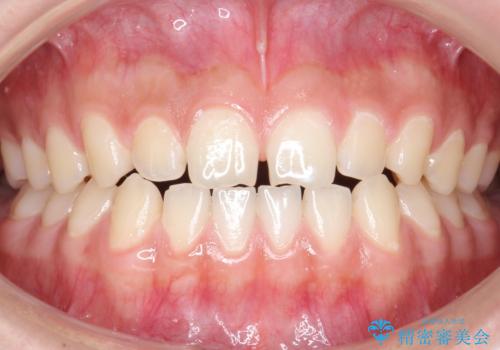

前歯のがたがた 前歯が内側に傾いている

- 2年3ヶ月

- 前歯のがたがたを主訴に来院。

上の歯並びが前にずれて、さらに前歯が内側に倒れて過蓋咬合を呈していました。